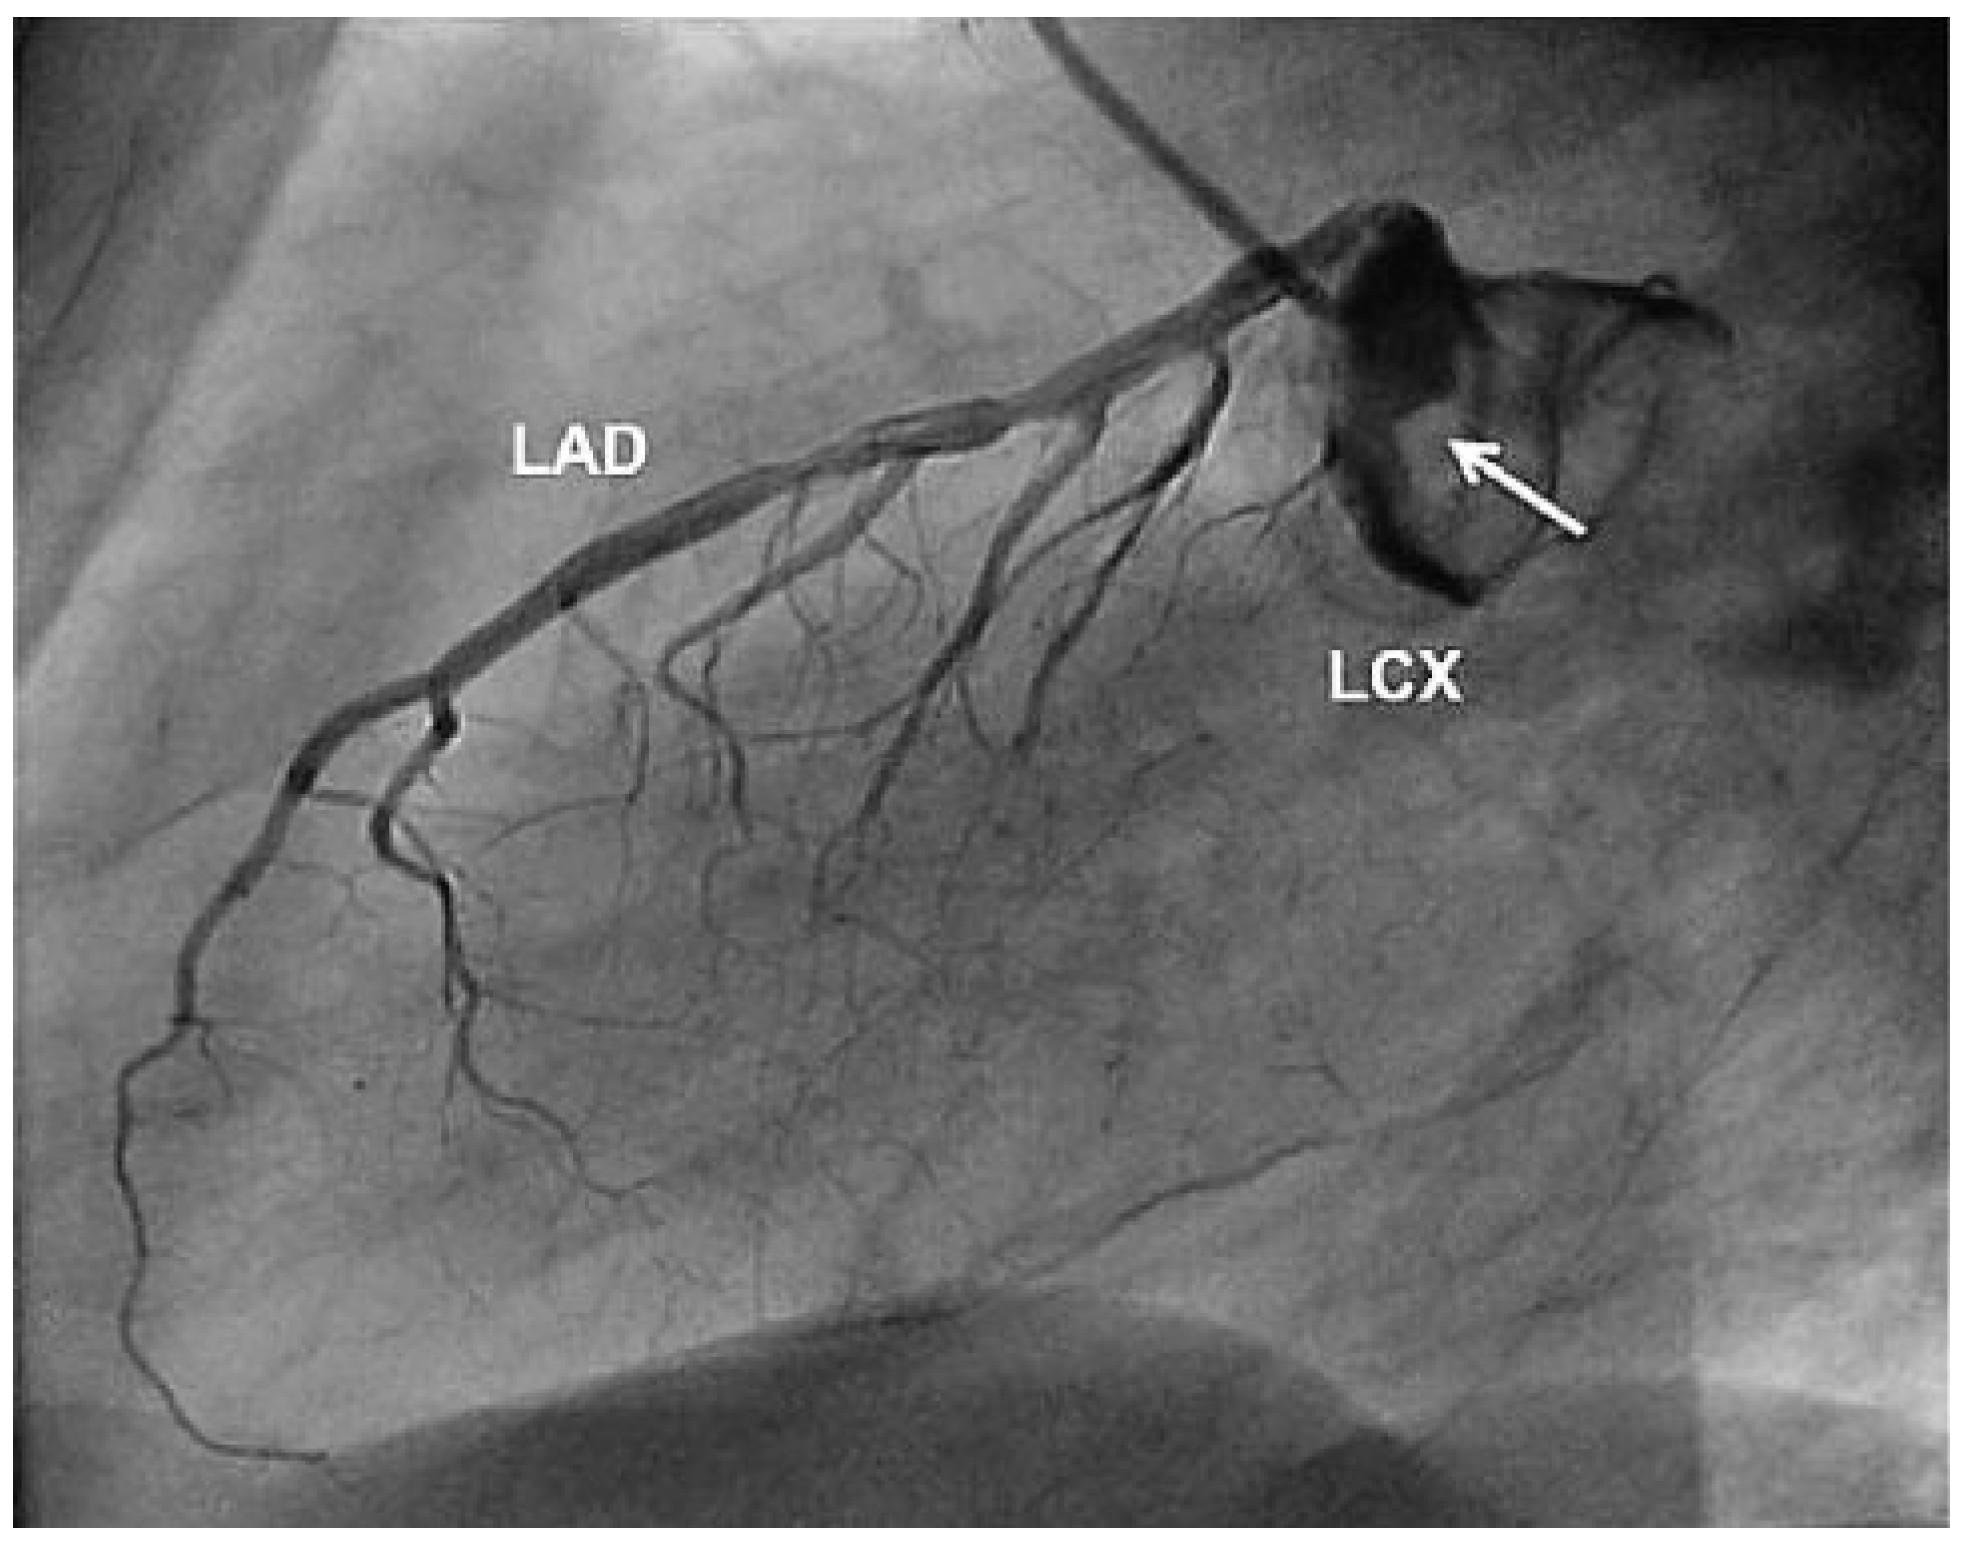

Aneurysm of the Left Circumflex Coronary Artery